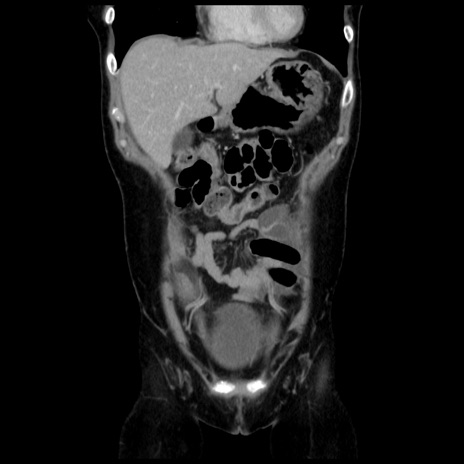

横断像

【症例】 50歳代女性

【主訴】 腹痛

【現病歴】前日生レバーを食べた。今朝に排便あり。 昼前に突然発症の腹痛を生じ、当院救急外来を受診した。

【既往歴】 子宮筋腫にてで子宮全摘後

【身体所見】 意識清明、腹部:平坦、軟、下腹部やや左を中心に圧痛・反跳痛あり、筋性防御あり

【データ】WBC 7800、CRP 0.07